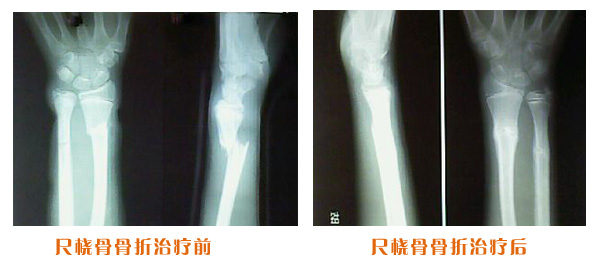

肥城市安駕莊梁氏骨科醫(yī)院是一所以梁氏手法正骨配合膏藥為特色的現(xiàn)代化專(zhuān)科醫(yī)院。

梁氏骨科術(shù)始創(chuàng)于清雍正年間,歷經(jīng)八代,至今已有三百年歷史。據(jù)1929年泰安縣志載“梁瑞圖先生,字增生,號(hào)蓮峰,安駕莊人,精岐黃并發(fā)明接骨,凡跌打車(chē)凡跌打車(chē)軋皮不破而碎骨者......【詳細(xì)】 |